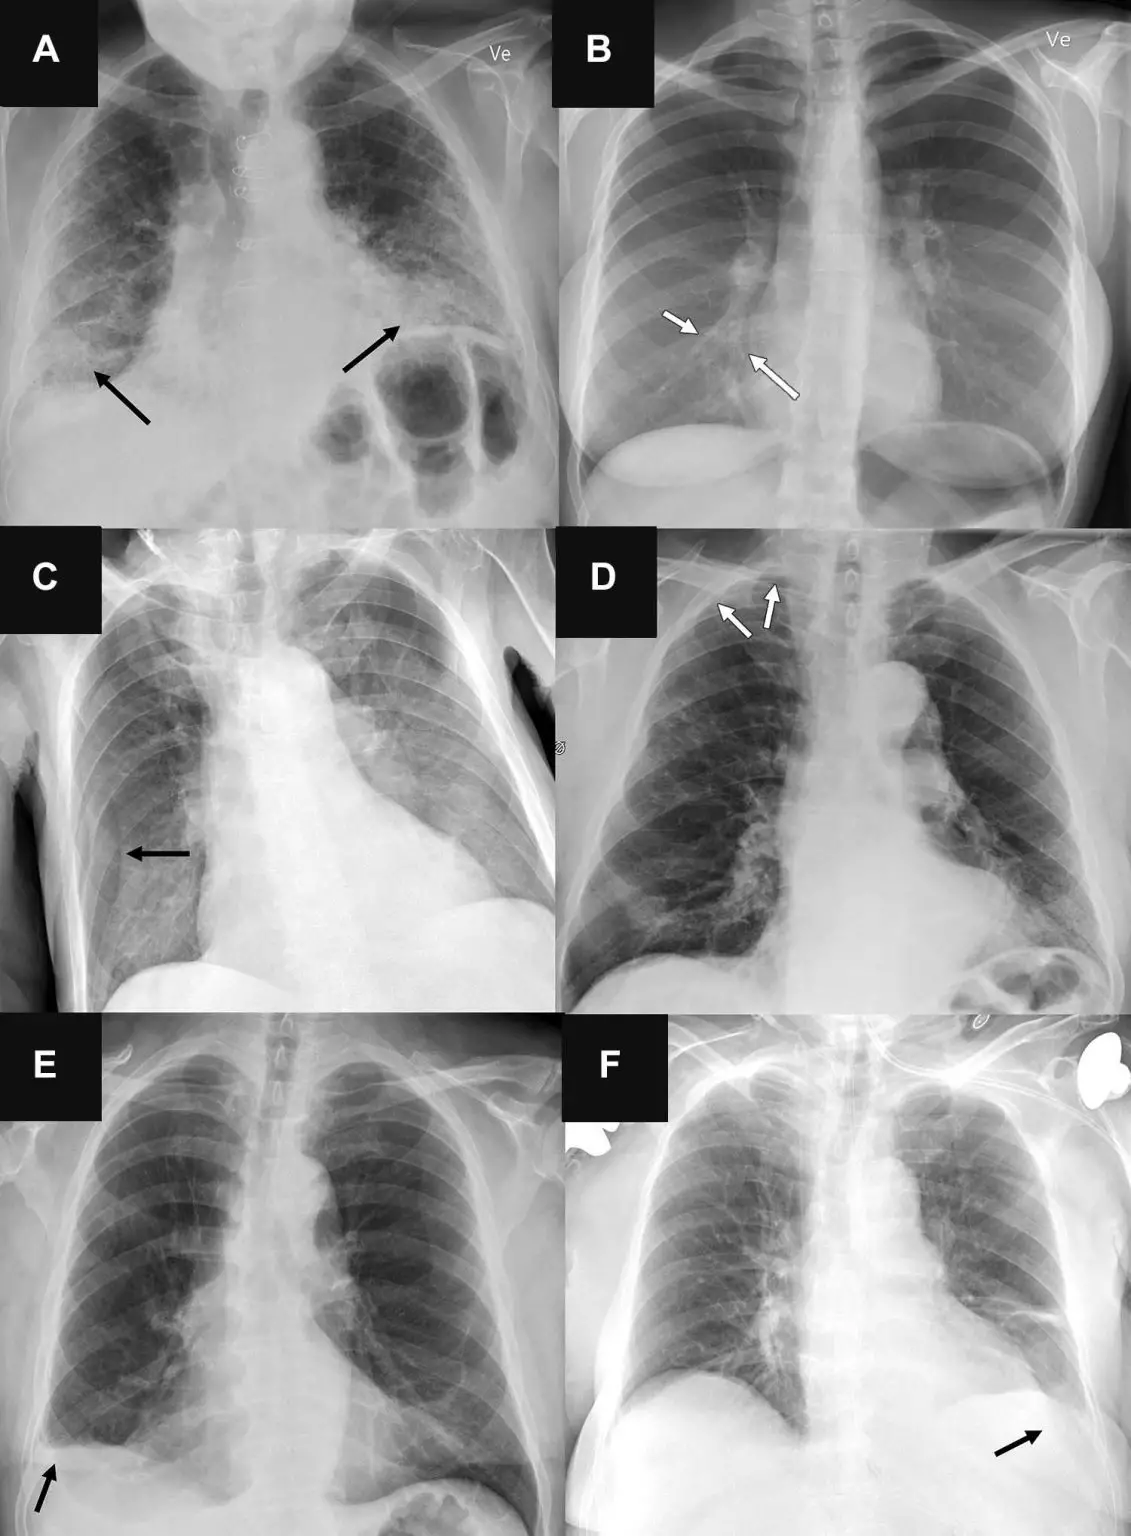

(A)71 岁男性患者因呼吸困难进展而接受检查的后前位胸部X 光片显示双侧纤维化(箭头 B)31 岁女性患者因咳嗽一个月而转诊接受放射检查的后前位胸部X 光片显示右心边界处有细微的气隙不清晰(箭头)。(C) 一名 78 岁男性患者在置入中心静脉导管后转诊的前胸X光片显示右侧皮肤皱褶(箭头)。(D)为排除气胸而转诊的一名 78 岁男性患者的后前方胸部 X 光片显示右侧顶部有一个非常细微的气胸(箭头)。(E)一名 72 岁男性患者的后正位胸部X光片显示肋膈角慢性变圆(箭头),该患者无特殊原因转诊进行放射检查。(F) 因怀疑充血和/或肺炎而转诊的 76 岁女性患者的前胸X光片显示左侧胸腔有非常微小的积液(箭头),所有三种能分析前胸X光片胸腔积液的人工智能工具都漏诊了。资料来源:北美放射学会